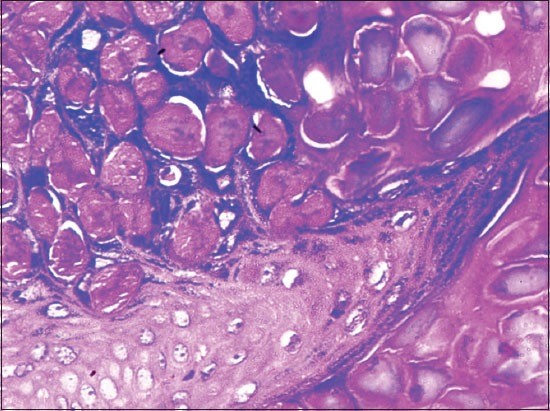

Giant Molluscum Contagiosum Opportunistic Infection in a HIV/AIDS Patient